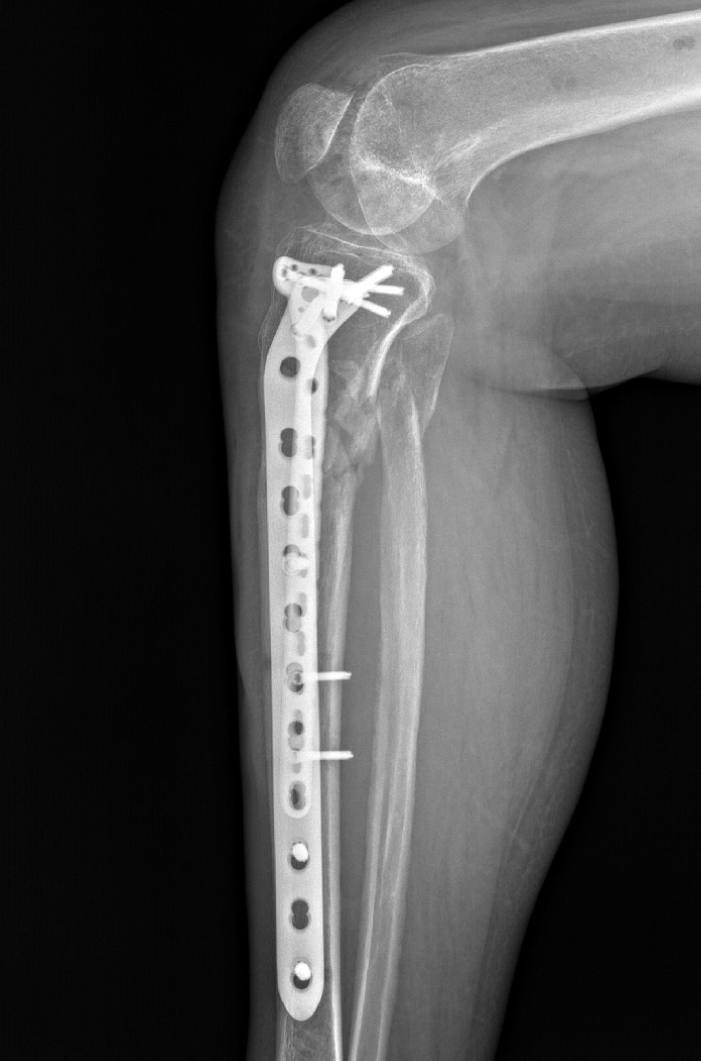

Післяопераційний період проходив без ускладнень і на 10 день після поступлення було проведено наступне етапне оперативне втручання: відкрита репозиція, металоостеосинтез пластинами.

Пацієнтка якісно провела реабілітацію і вже зараз починає навантажувати травмовану кінцівку, щоб згодом повернутися на роботу!